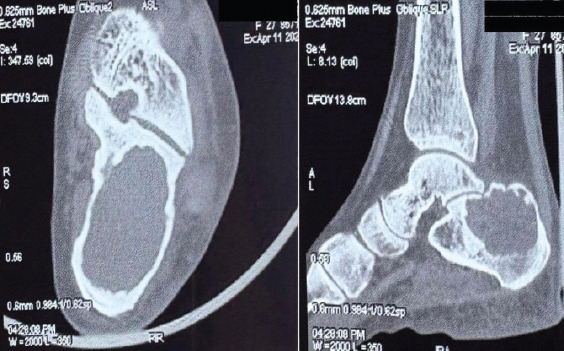

Case report: Benign bone tumors such as GCT are often diagnosed with a symptomatology typical of bone tumors, however, there have been many reported cases wherein they were diagnosed incidentally as part of investigation into a different disease manifestation. These nuances are of more significance in case of GCT as it is a benign aggressive tumor and the prognosis after treatment is highly dependent on earlier diagnosis allowing for increased chances at limb salvage and functional restoration as compared to more radical treatment options.Lateral ankle sprain is a commonly encountered disease entity and, as such, enjoys a very benign progression with conservative management.Our patient was initially diagnosed on outpatient basis as a case of ankle sprain based on the history and clinical features, However, worsening of symptoms on conservative management prompted us toward the presence of a more sinister pathology. Subsequent radiological and histopathological investigations helped in the definitive diagnosis of GCT of calcaneus.